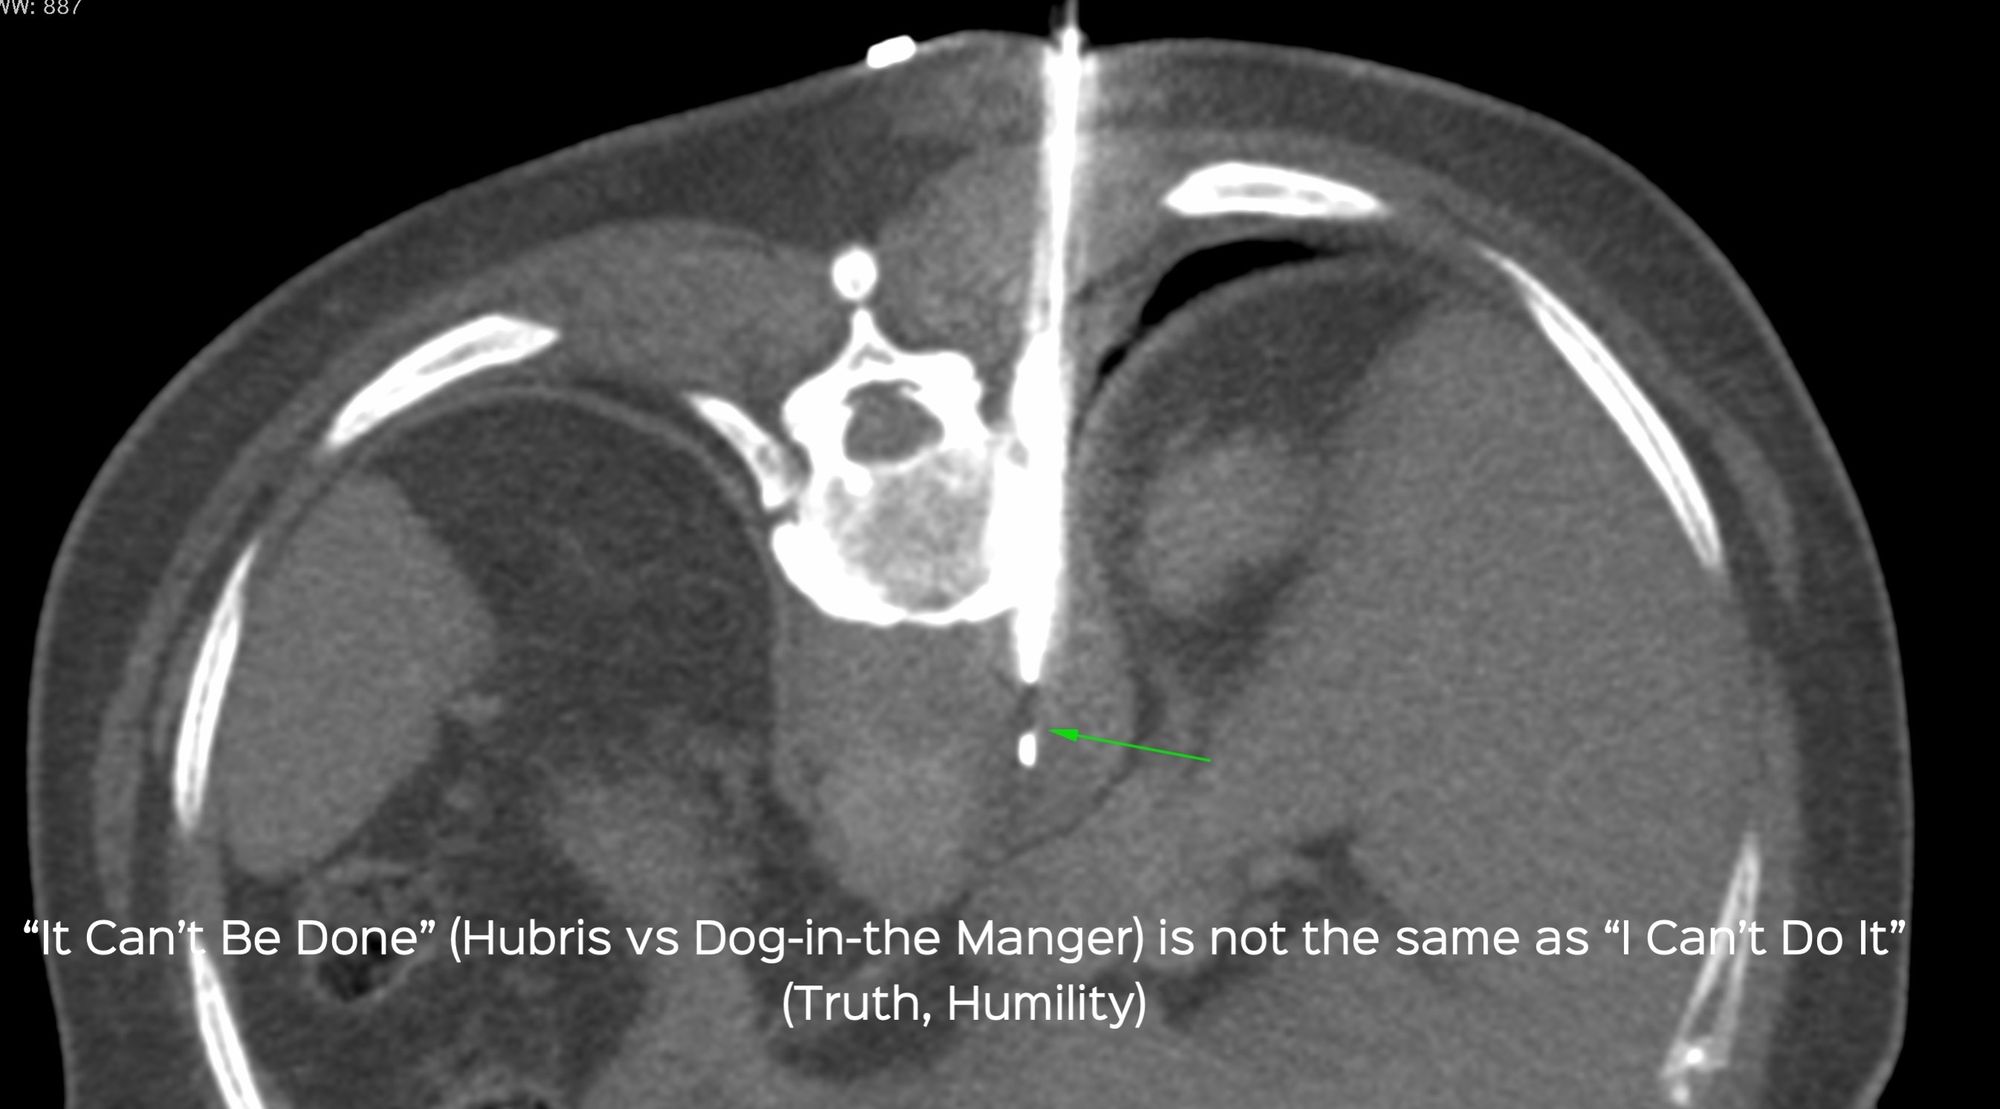

Case 33: Retrocrural Mass Biopsy - The Difference Between "It Can't Be Done" and "I Can't Do It"

Bhavin Jankharia - 15 May 2021